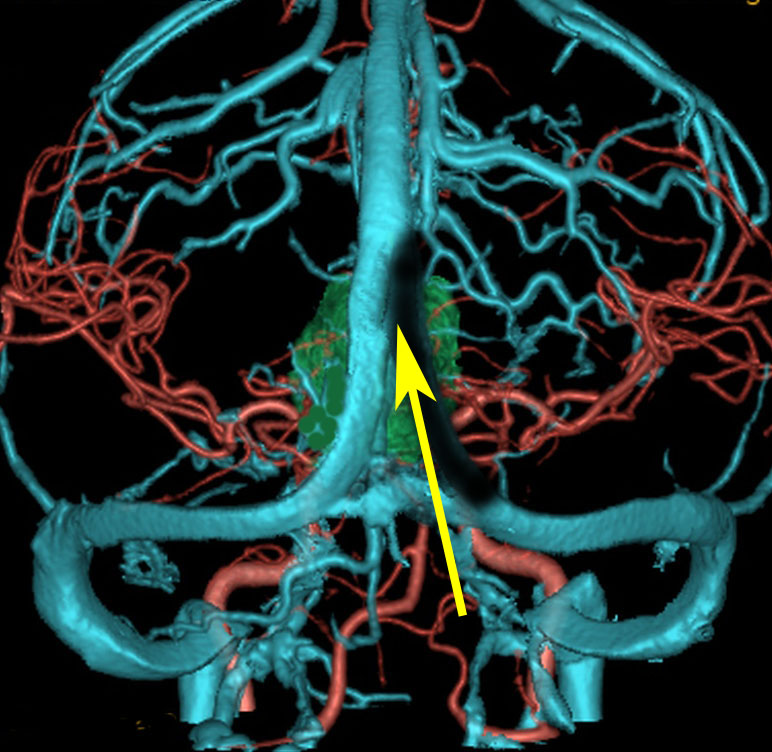

松果体腫瘍へのOTAのルートです。occipital transtentorial apporachというのは黄色の矢印に沿ってガレン大静脈の下に入る方法であり,そこから松果体部を通って第3脳室内へ直線的な視野が展開します。

一方,赤の矢印に沿ったルートは parieto-occipital transtentorial approachです。このルートでは内大脳静脈 internal cerebral veins を見ることがかなり難しいです。更に,第3脳室に入るためには脳梁膨大部 spleniumを切断する必用があります。ただし,小脳上部や第4脳室を見るときにはparietal寄りのルートを使います。

この2つのルートを混同している脳外科の先生はとても多いと思います。OTAとは,外後頭隆起を削除して,後頭極(後頭葉)を牽引して,テントの全長を切開しなければ遂行できない到達法であることを認識して下さい。

さらに要点としては,静脈洞交会 confluence に近いところに視軸がくるので,横静脈洞と上矢状静脈洞の交点のギリギリまで硬膜切開をする必用があります。松果体部から第3脳室に入るためにはローゼンタール静脈を十分剥離して可動化し,左右の術野展開をして行きます。